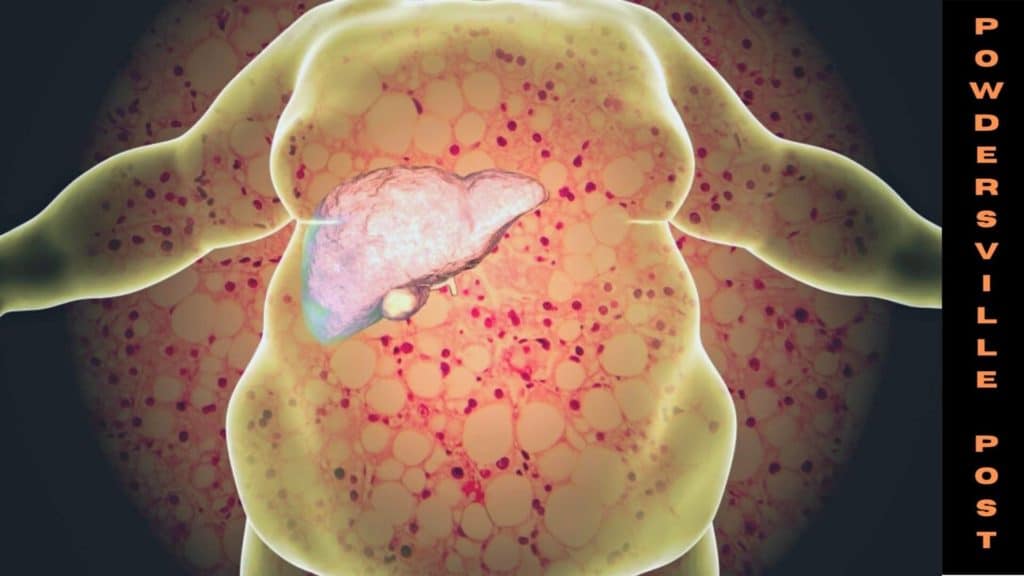

Nikki Attkisson | Last Updated : December 30, 2021Fatty liver disease, or hepatic steatosis, is a dangerous ailment requiring medical diagnosis due to the storage of extra fat in the liver. The medical fraternity has so far been perplexed by this liver ailment, due to the absence of any known causes and symptoms.

Non-alcoholic fatty liver disease (NAFLD) has been the subject of numerous studies and research due to its evolving nature, causing more deaths worldwide at an increasing rate in the last few decades.

The two commonly understood causes of NAFLD are excessive alcohol consumption and obesity. However, there is no substance or wide-scale accepted research that can substantiate the causation.

A common cause of fatty liver disease is high levels of alcohol consumption, though, it is not the only cause. The disease also occurs due to other conditions like excessive intake of calories and the presence of other conditions like diabetes and obesity.

BUPA mentioned 5 factors that could potentially increase the risk of fat building up in the liver, which is High Blood pressure, Extreme fat in the body, Type 2 Diabetes, Inheritance, and Extra weight around the middle of the body.

Being a symptom-less condition, NAFLD is challenging to detect unless it has progressed at an advanced stage. Medical experts have suggested that early detection of the condition is necessary to prevent liver failure, cirrhosis, and in some cases, liver cancer.